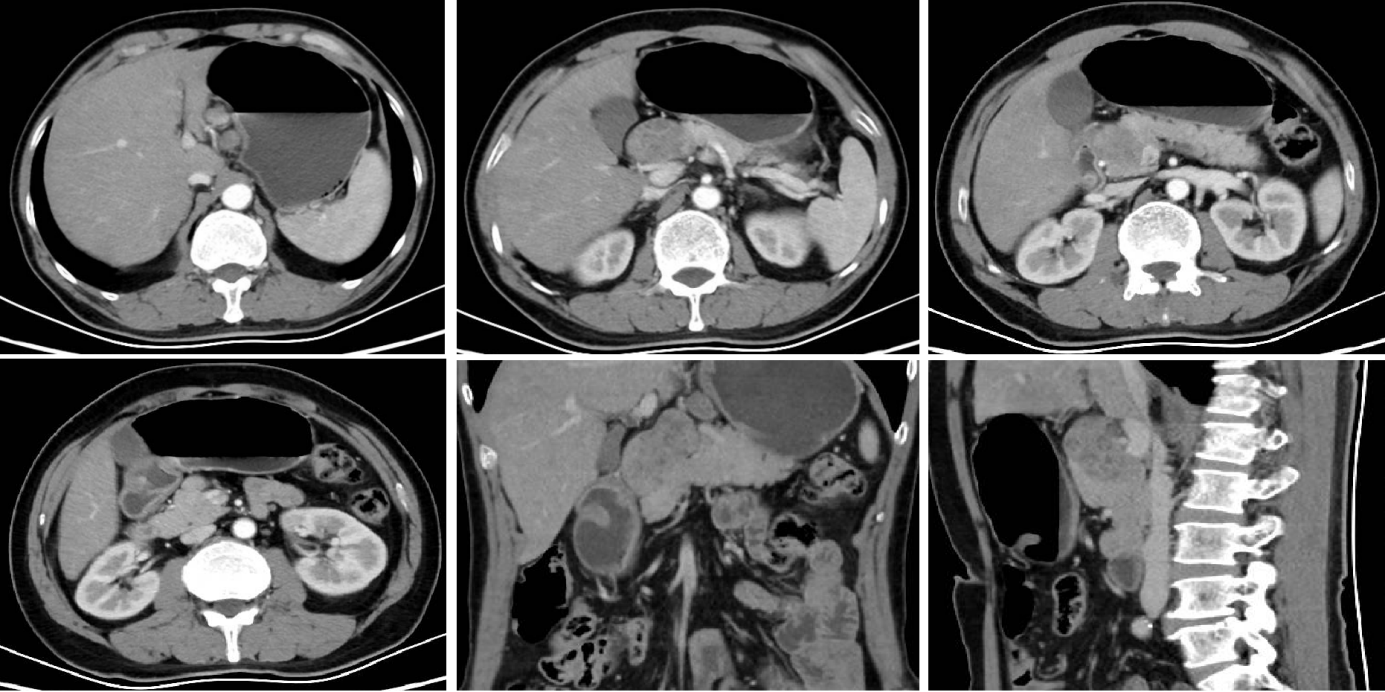

2024-03-12腹盆CT回报:对比2024-01-19腹盆CT:胃窦部胃壁增厚减轻,较厚处原约12mm,现约9mm,与正常胃壁分界不清,浆膜面模糊。No.1-3,7-8,9组多发淋巴结,部分增大,较大原约34*31mm,现约46*31mm,与胰腺分界欠清(图2)。临床疗效评价:综合考虑PD。

2024-04-12行第2周期行维迪西妥单抗+伦伐替尼+替雷利珠单抗治疗。2024-04-26、2024-05-03行第3周期行维迪西妥单抗+伦伐替尼+替雷利珠单抗治疗,过程中监测见患者AFP持续下降,2024-03-28为630.4ng/ml,2024-05-02为102.3ng/ml。期间于2024-04-24复查CT示:对比2024-03-12 腹盆部CT:胃窦部胃壁增厚大致同前,较厚仍约9mm,增强扫描强化明显。No.1-3,7-8,9组多发淋巴结部分缩小,较大原约46*31mm,现约25*22mm,与胰腺分界欠清。

2024-05-28再次复查CT示:对比2024-04-24腹盆部CT:胃窦部胃壁增厚大致同前,较厚仍约9mm,增强扫描强化明显。No.1-3,7-8,9组多发淋巴结部分缩小,较大原约25*22mm,现约14*13mm,与胰腺分界欠清(图3)。临床疗效评价:PR。